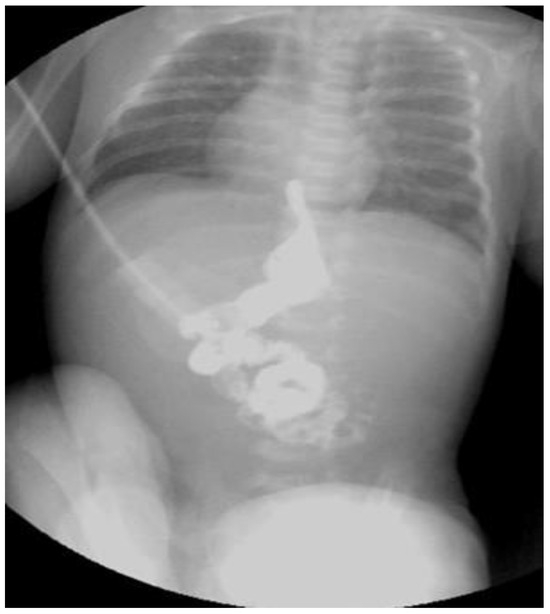

EA associating DA and perineal fistula: case 5

EA associating imperforate anus without fistula: case 6